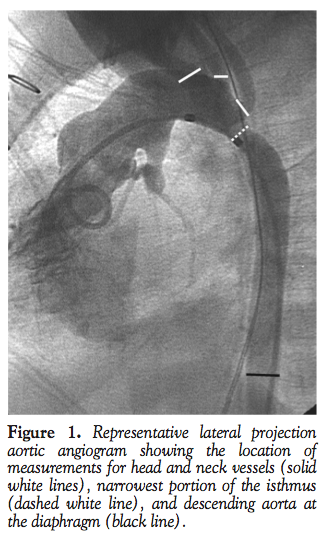

We retrospectively identified patients with HLHS who had at least one catheterization with aortic angiography after NO from 2002 through 2011. Data collected for all catheterizations included demographics, hemodynamics, aortic arch branching pattern, measurements of the diameters of all head and neck vessels proximal to the isthmus, narrowest portion of the isthmus and the descending aorta at the diaphragm, or the most distal portion visible in the angiogram (Figure 1). For patients with NAAO who underwent balloon aortoplasty, measures of the isthmus and descending aorta were repeated post intervention. All measurements were made from lateral projections of aortic angiograms.

The diameters of the head and neck vessels were totaled and divided by the narrowest diameter of the aortic isthmus to give a head and neck index (HNI). A higher HNI was considered indicative of possible NAAO. For comparison, two other measures were calculated: (1) coarctation index (CI), by dividing the narrowest diameter of the isthmus by the descending aorta at the diaphragm; and (2) the narrowest diameter of the isthmus indexed to body surface area (Isth). A value ≤0.5 was used to define a significantly small CI, as used by Porras and colleagues;2 smaller values of Isth were considered indicative of possible NAAO.